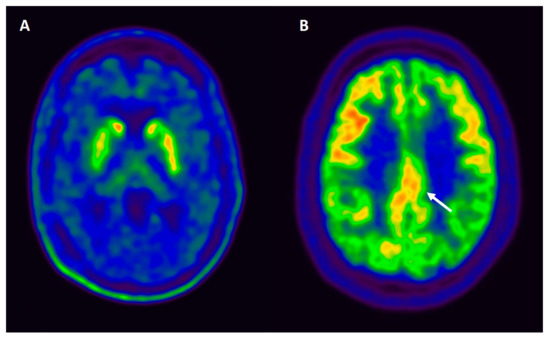

Loss of the neurons in SN is extensive and characteristic for PD and DLB, and leads to a substantial reduction in the striatal presynaptic dopaminergic function showed by a reduction on presynaptic dopamine transporter (DAT) or 18F-dopa uptake [144] (see Figure 3A). Reduced DAT uptake in basal ganglia demonstrated by SPECT or PET imaging has shown to be useful in distinguishing DLB from AD, based on sensitivity (78%) and specificity (90%) [145]. Moreover, some studies have evaluated the sensitivity of DAT in distinguishing prodromal stages of Lewy body disorders from AD, with a sensitivity of 54% and specificity of 89% [20]. Although an abnormal DAT scan supports the diagnosis of DLB [14], a normal scan does not exclude DLB altogether, including those cases that present with minimal motor symptoms [146], and does not distinguish between PDD and DLB.

Figure 3. (A) Axial 18F-Dopa PET image of a patient with dementia with Lewy bodies. The image shows a moderate decrease of bilateral striatal activity (dopaminergic denervation), more pronounced in the right putamen. (B) FDG-PET findings in a patient with dementia with Lewy bodies. Axial FDG-PET image demonstrates the cingulate island sign (indicated with an arrow), which reflects preservation of posterior cingulate metabolism relative to cuneus and precuneus.

Cerebral perfusion SPECT evaluates the metabolic status of brain tissue by quantifying changes in the regional cerebral blood flow. Occipital hypoperfusion is frequently observed in DLB; however, it was unable to differentiate PDD cases from DLB, revealing similar perfusion profiles in some studies [147]. Occipital hypometabolism combined with a less prominent metabolic decrease in the medial temporal lobe using F-18 fluoro-deoxy-glucose (FDG) PET may be useful in differentiating DLB and PDD from AD [148]. Moreover, the relatively preserved metabolism in the posterior cingulate cortex in DLB, also known as the “cingulate island” sign, achieved the highest sensitivity (100%) in differentiating DLB from AD, and is also included as a supportive biomarker in the diagnostic criteria of DLB [14] (see Figure 3B). A study directly comparing the accuracy of FDG-PET with SPECT perfusion found that the cingulate island sign was only present with FDG-PET imaging in DLB, but not with SPECT [149]. Patients with PDD showed large areas (occipitoparietal > frontal) of coincidental hypometabolism and atrophy, and the hypometabolism in PD appears to predate and is replaced by atrophy, in a progressive manner as the cognitive state worsens [150]. PDD and DLB often show similar patterns, but a more prominent hypometabolism in the anterior cingulate cortex may distinguish DLB from PDD [148]. The evaluation of the posterior cingulate cortex in PDD has not received attention compared to DLB, in which the preserved metabolism of this area (the cingulate island) has a high sensitivity and specificity in the differential diagnosis from AD [151,152].